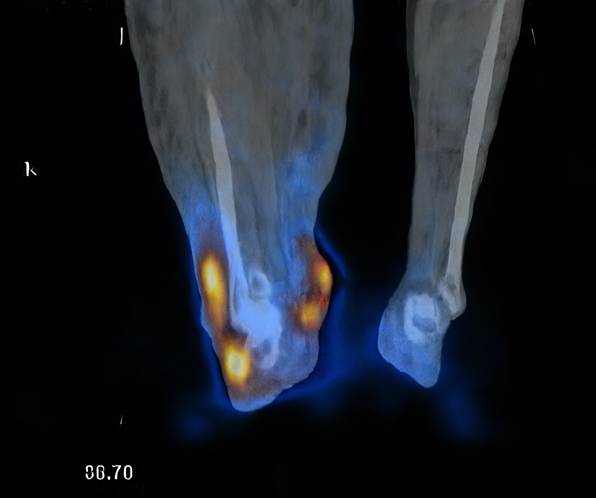

Seven patients underwent lymphoscintigraphy at 12 months. All demonstrated findings suggestive of functional improvement, including increased tracer uptake in the transferred omental flap (Figure 5), clearer visualisation of lymphatic trunks, reduced dermal backflow, and fewer collateral channels (Figure 6). Comparative analysis was not feasible in five patients due to flap failure (n = 1), loss to follow-up (n = 1), or incompatible preoperative imaging protocols (n = 3).

Figure 5

Radiotracer uptake detected in the omental flap (indicated by red dots).

These findings are consistent with previous reports by Ciudad et al.[12] and Nguyen et al. [18, 22], who demonstrated clinical and functional improvement following laparoscopic omental VLNT. Our results are further corroborated by recent extensive clinical experiences reported by Pozzi et al., which reaffirmed that gastroepiploic VLNT is a highly effective and safe procedure for extremity lymphedema, offering significant improvements in limb circumference and tissue tonicity with minimal donor-site morbidity [26]. Notably, our lymphoscintigraphy suggested not only improved drainage but also radiotracer uptake within the transferred flap, supporting the concept of neo-lymph node formation through lymphangiogenesis and functional integration into the host lymphatic network. This aligns with prior experimental studies showing that transplanted lymph nodes secrete VEGF-C and VEGF-D, which stimulate VEGFR-3-mediated lymphangiogenesis and promote the regeneration of lymphatic sinuses and high endothelial venules (HEVs) [12, 18, 22].

The observed greater reduction in distal limb circumference further supports the biological mechanism: placing the omental flap at the ankle optimises gravitational drainage and provides a local microenvironment for lymphangiogenesis. The improved uptake and reduced dermal backflow on lymphoscintigraphy are consistent with the establishment of new lymphatic pathways and the functional maturation of neo-lymph nodes.